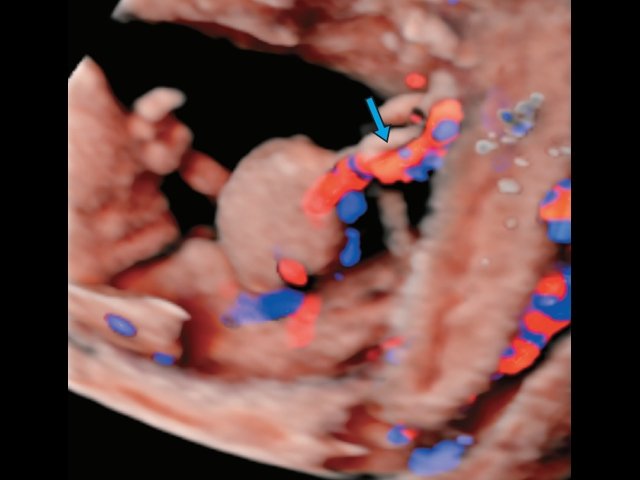

Также стоит отметить, что если раньше большинство генетических синдромов диагностировалось на поздних сроках беременности, начиная со сроков 25–26 нед, то с техническим прогрессом в развитии ультразвуковых сканеров связана настоящая «революция» так называемого генетического ультразвука, что сказалось как на сроках выявления, так и на огромном количестве новых диагностических возможностей, позволяющих пренатально диагностировать наследственную патологию у плода [11]. Например, расщелины верхней губы и твердого нёба можно диагностировать не только в сроки второго скринингового осмотра в 20–21 нед (рис. 33–35), но и при первом анатомическом скрининговом УЗИ в 11–14 нед беременности (рис. 36). Применение новейших дуплексных режимов, совместно с цветовым допплеровским картированием позволяет диагностировать врожденные пороки сердца и сосудов, начиная с ранних сроков (рис. 37), особенности строения пуповины (рис. 38, 39).

Рис. 37. Общий артериальный ствол, 13 нед беременности.